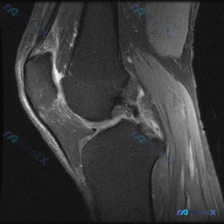

这是一份膝关节MRI矢状位T1加权图像,我们先整理所有客观观察:

- 骨骼与骨髓:股骨远端、胫骨近端、髌骨骨皮质完整,无骨质破坏断裂;骨髓信号大致均匀,无局灶性异常低信号,不支持骨髓水肿、肿瘤浸润

- 交叉韧带:后交叉韧带连续性好,走行形态正常;前交叉韧带(ACL)连续性尚可,但胫骨止点和走行中段信号增高模糊,形态稍平直、张力异常

- 半月板:可见层面内半月板形态、信号基本正常,无明确穿透关节面的高信号提示撕裂

- 伸膝装置:股四头肌腱、髌腱走行信号均正常

- 关节与软组织:关节软骨轮廓尚可,髌下脂肪垫信号正常,无显著关节积液;髌骨后方关节面可见少量细微信号变化

这份图像里的明确异常其实不在软骨,核心异常集中在前交叉韧带:ACL不是正常的均匀低信号带,信号欠均匀,提示可能存在陈旧性损伤后纤维化、轻微部分撕裂或者韧带内变性。

而题干提到的软骨异常,仅在髌骨后方看到少量细微信号变化,因为T1序列对软骨病变敏感度本来就低,这个发现需要谨慎解读,更可能是继发改变。

用一元论来解释这个病例其实非常清晰:核心是ACL的陈旧性损伤或变性,继发膝关节不稳,进而导致髌骨后方软骨磨损,刚好可以解释所有影像发现。

不过这里必须提醒大家:T1序列本身对骨髓水肿、细微软骨损伤、半月板撕裂、关节积液的检出能力非常有限,现在的判断只是基于现有序列的推断,要明确诊断必须补充PD/T2加权脂肪抑制序列,同时结合临床病史和体格检查(Lachman试验、前抽屉试验等)进一步确认。